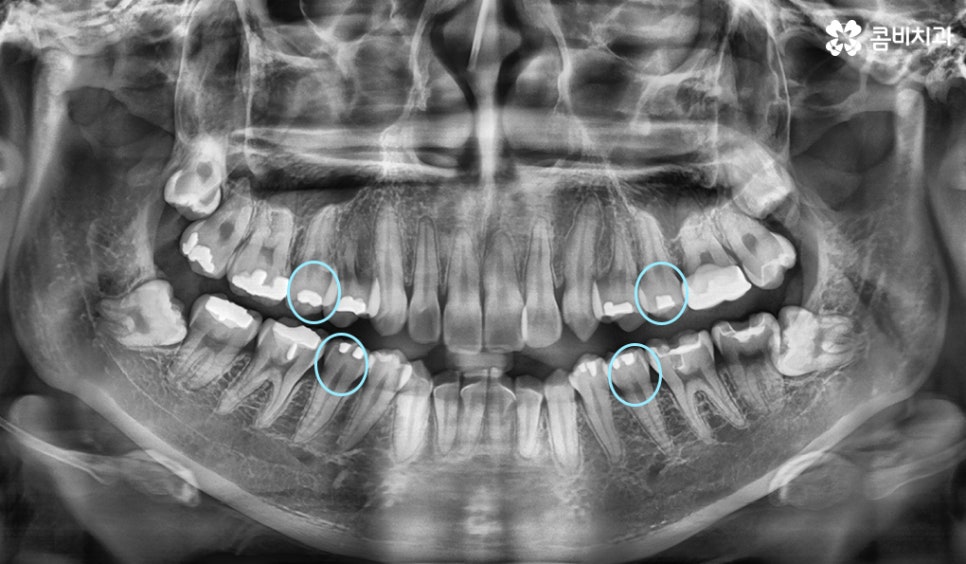

엑스레이에서 동그라미를 그린 4군데를 발치하여 교정이 진행된 사례

위 환자분의 사례는 현재 치열 상태와 골격, 얼굴형을 정밀

검진하여 시술 후 결과에 대한 시뮬레이션을 하였을 때

치열뿐 아니라 돌출입의 개선을 함께 목표로 진행이 되었기

때문에 콤비교정 전에 발치를 하게 된 케이스입니다.